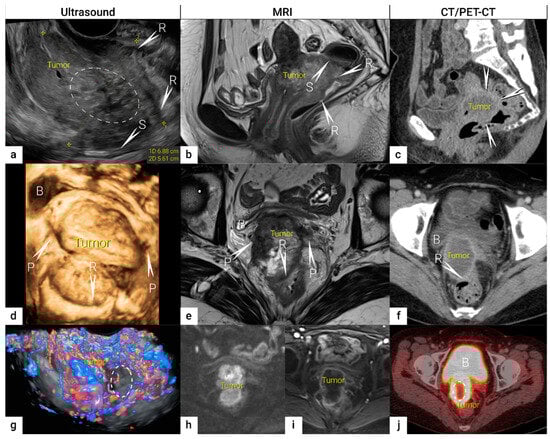

3.1. Tumour Detection

3.2. Tumour Delineation within Cervix (Tumour Size, Depth of Stromal Invasion, Minimum of Uninvolved Stroma, and Cranial Tumour-Free Margin)

3.3. Extrauterine Extension (Vagina, Parametria, Pelvic Side Wall, Hydronephrosis and Others)

| IB | Carcinoma with deepest stromal invasion >5 mm, limited to the cervix uteri with size measured by maximum tumour diameter. | US: Highly vascularised hypoechogenic (squamous-cell carcinoma) or iso-/hyperechogenic lesion (adenocarcinoma) with intact hyperechogenic pericervical fascia and positive sliding sign between tumour and bladder/rectum. MRI: Tumour has intermediate to high signal on T2W images. Dynamic CE-T1W images depicts tumour as hyperintense in the arterial phase and iso- or hypointense in the venous phase. Tumours characteristically exhibit restricted diffusion on DWI (hyperintensity on high b-value images and low intensity on the ADC maps). Tumour does not disrupt the hypointense peripheral stromal ring (best seen on T2W images). | |